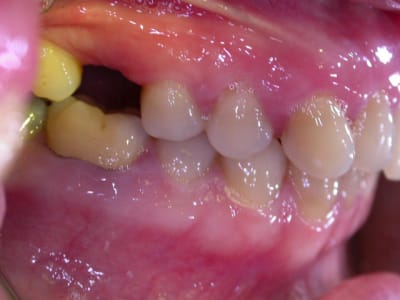

examen buccal .........voir les photos ........après ........ca vient

examen radio .........après ca vient.......

Bon controle de plaque, pas de tartre ni de colorations, inflammation en palatin seulement...